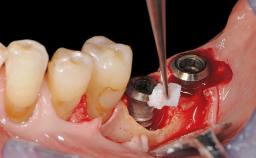

Reconstructive Treatment of a Peri-Implantitis Defect at an Implant in a Mandibular Molar Site

In this case, Mario Roccuzzo utilizes surgical bone regeneration treatment around implant 46 using a bone graft substitute and a connective tissue graft to resolve peri-implant inflammation, reduce the probing depths, and prevent further progression of disease.

A 58-year-old-male patient was referred in February 2007 for implant placement in the right mandibular molar area. Two tissue level implants were inserted at sites 44 and 46, respectively, to support a three-unit fixed dental prosthesis (FDP).